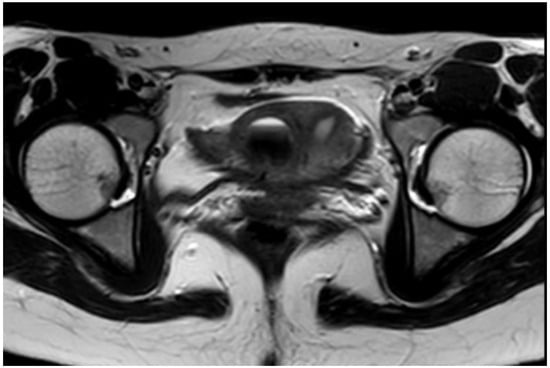

- O21. Vaginoresectoscopy in the Treatment of Ohvira in Adolescent Girls of the Russian Federation

Introduction: OHVIRA syndrome is an obstruction of the hemivagina in the presence of a kidney anomaly on the ipsilateral side. The therapeutic approach in the management of such patients is to carry out surgical treatment in order to minimize complications and improve the quality of life. The classic method of treatment is to perform reconstructive plastic surgery in the volume of instrumental defloration and vaginal correction. This approach is characterized by long-term operating room occupancy and the risk of intraoperative complications. Previously described resectoscopic dissection of the asymmetric septum pointing out the high efficiency and low percentage of complications.

Aim of the Study: To evaluate the effectiveness and safety of vaginoresectoscopy in the treatment of OHVIRA.

Methods: 130 patients with OHVIRA were treated at the Pediatric and Adolescent Gynecology department from 2021 to 2023 y. According to the classical method n = 46, using vaginoresectoscopy according to the improved method n = 72. The average duration of the operation, blood loss, complaints in the early postoperative period, early and late complications were evaluated.

Results: The average duration of surgery in the main group (vaginoresectoscopy method) was 38.4 min versus 98.8 min in the comparison group; blood loss in the main group averaged 7.8 mL versus 55.2 mL in the comparison group; it should be noted that in most cases the girls noted the absence of any complaints affecting the general well-being already on the 1st day after the intervention, determining by VAS—the absence of pain. During the follow-up period from 2021 to the present, in the main group, stricture of the formed vagina was detected in 2.7% versus 4.3% in the comparison group.

Conclusions: Vaginoresectoscopy is an effective and safe method of surgical treatment for obstructive genital abnormalities.